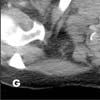

The lesion in the right supraclavicular region is visible on the superior aspect of the study (G, arrow). Images in lung windows, surprisingly, are unrevealing, as are images of the more cephalad aspects of the neck.